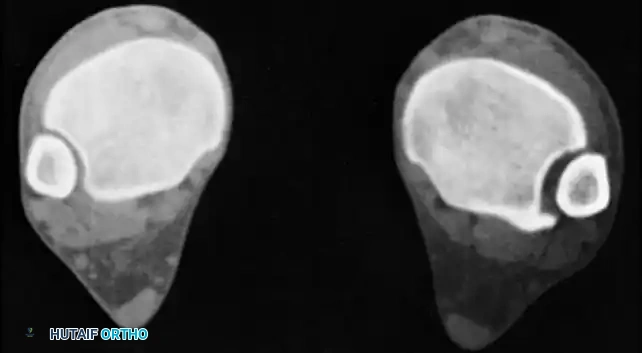

يعتبر التصوير الطبي المتقدم، وخاصة التصوير المقطعي المحوسب، أمراً إلزامياً لتقييم حالات الالتئام الخاطئ المشتبه بها، خاصة النوع الخفي. اتساع المفصل الليفي الظنبوبي الشظوي في المقاطع المحورية هو علامة مميزة على قصر الشظية والدوران الخارجي، وهي تفاصيل قد لا تظهر بوضوح في الأشعة السينية التقليدية.